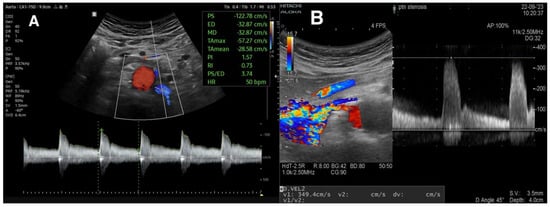

3.2.2. Peak Systolic Velocity and Renal–Aortic Ratio

3.2.3. Acceleration Time and Acceleration Index